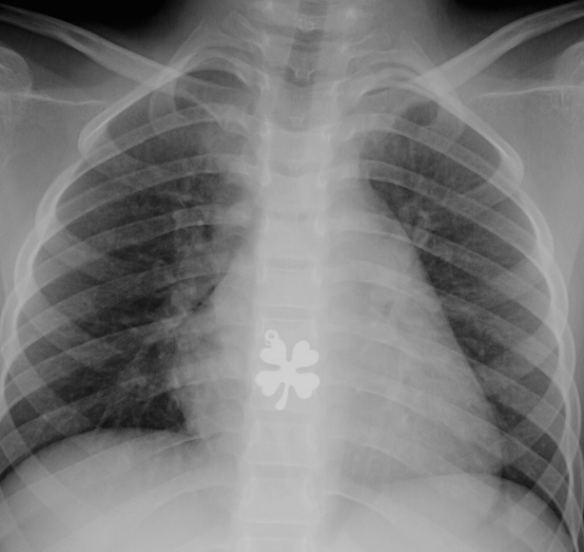

Radiologic Image for St. Patrick’s Day Posted on March 17, 2015 by gutsandgrowth Image of esophageal foreign body ingestion: Ingested 4-Leaf Clover Pendant -Courtesy of Steven Liu Share this: Email a link to a friend (Opens in new window) Email Share on X (Opens in new window) X Share on Facebook (Opens in new window) Facebook Like Loading... Related